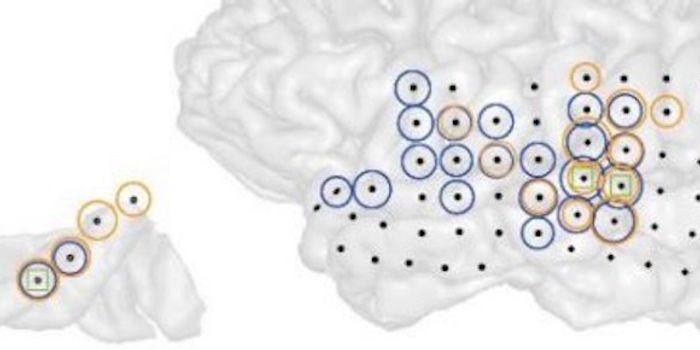

JUN 30, 2016NeuroscienceWhen there has been a traumatic brain injury (TBI) or there is a tumor or other problem in the brain, doctors need to kn ...